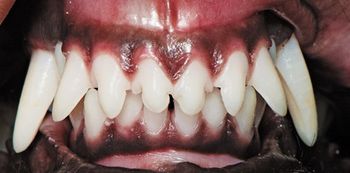

What approach would you take to fix this pups tooth and provide a solution for the long term?

Scan the photos, spot the answer and save the patient.

Extraction isn't always the best choice for veterinary patients with tooth troubles. Find out in which cases tooth repair-not removal-can restore dental health.

When is dental extraction the treatment of choice? Find out in this first installment of a multipart series on what to do to when faced with dental pathology.